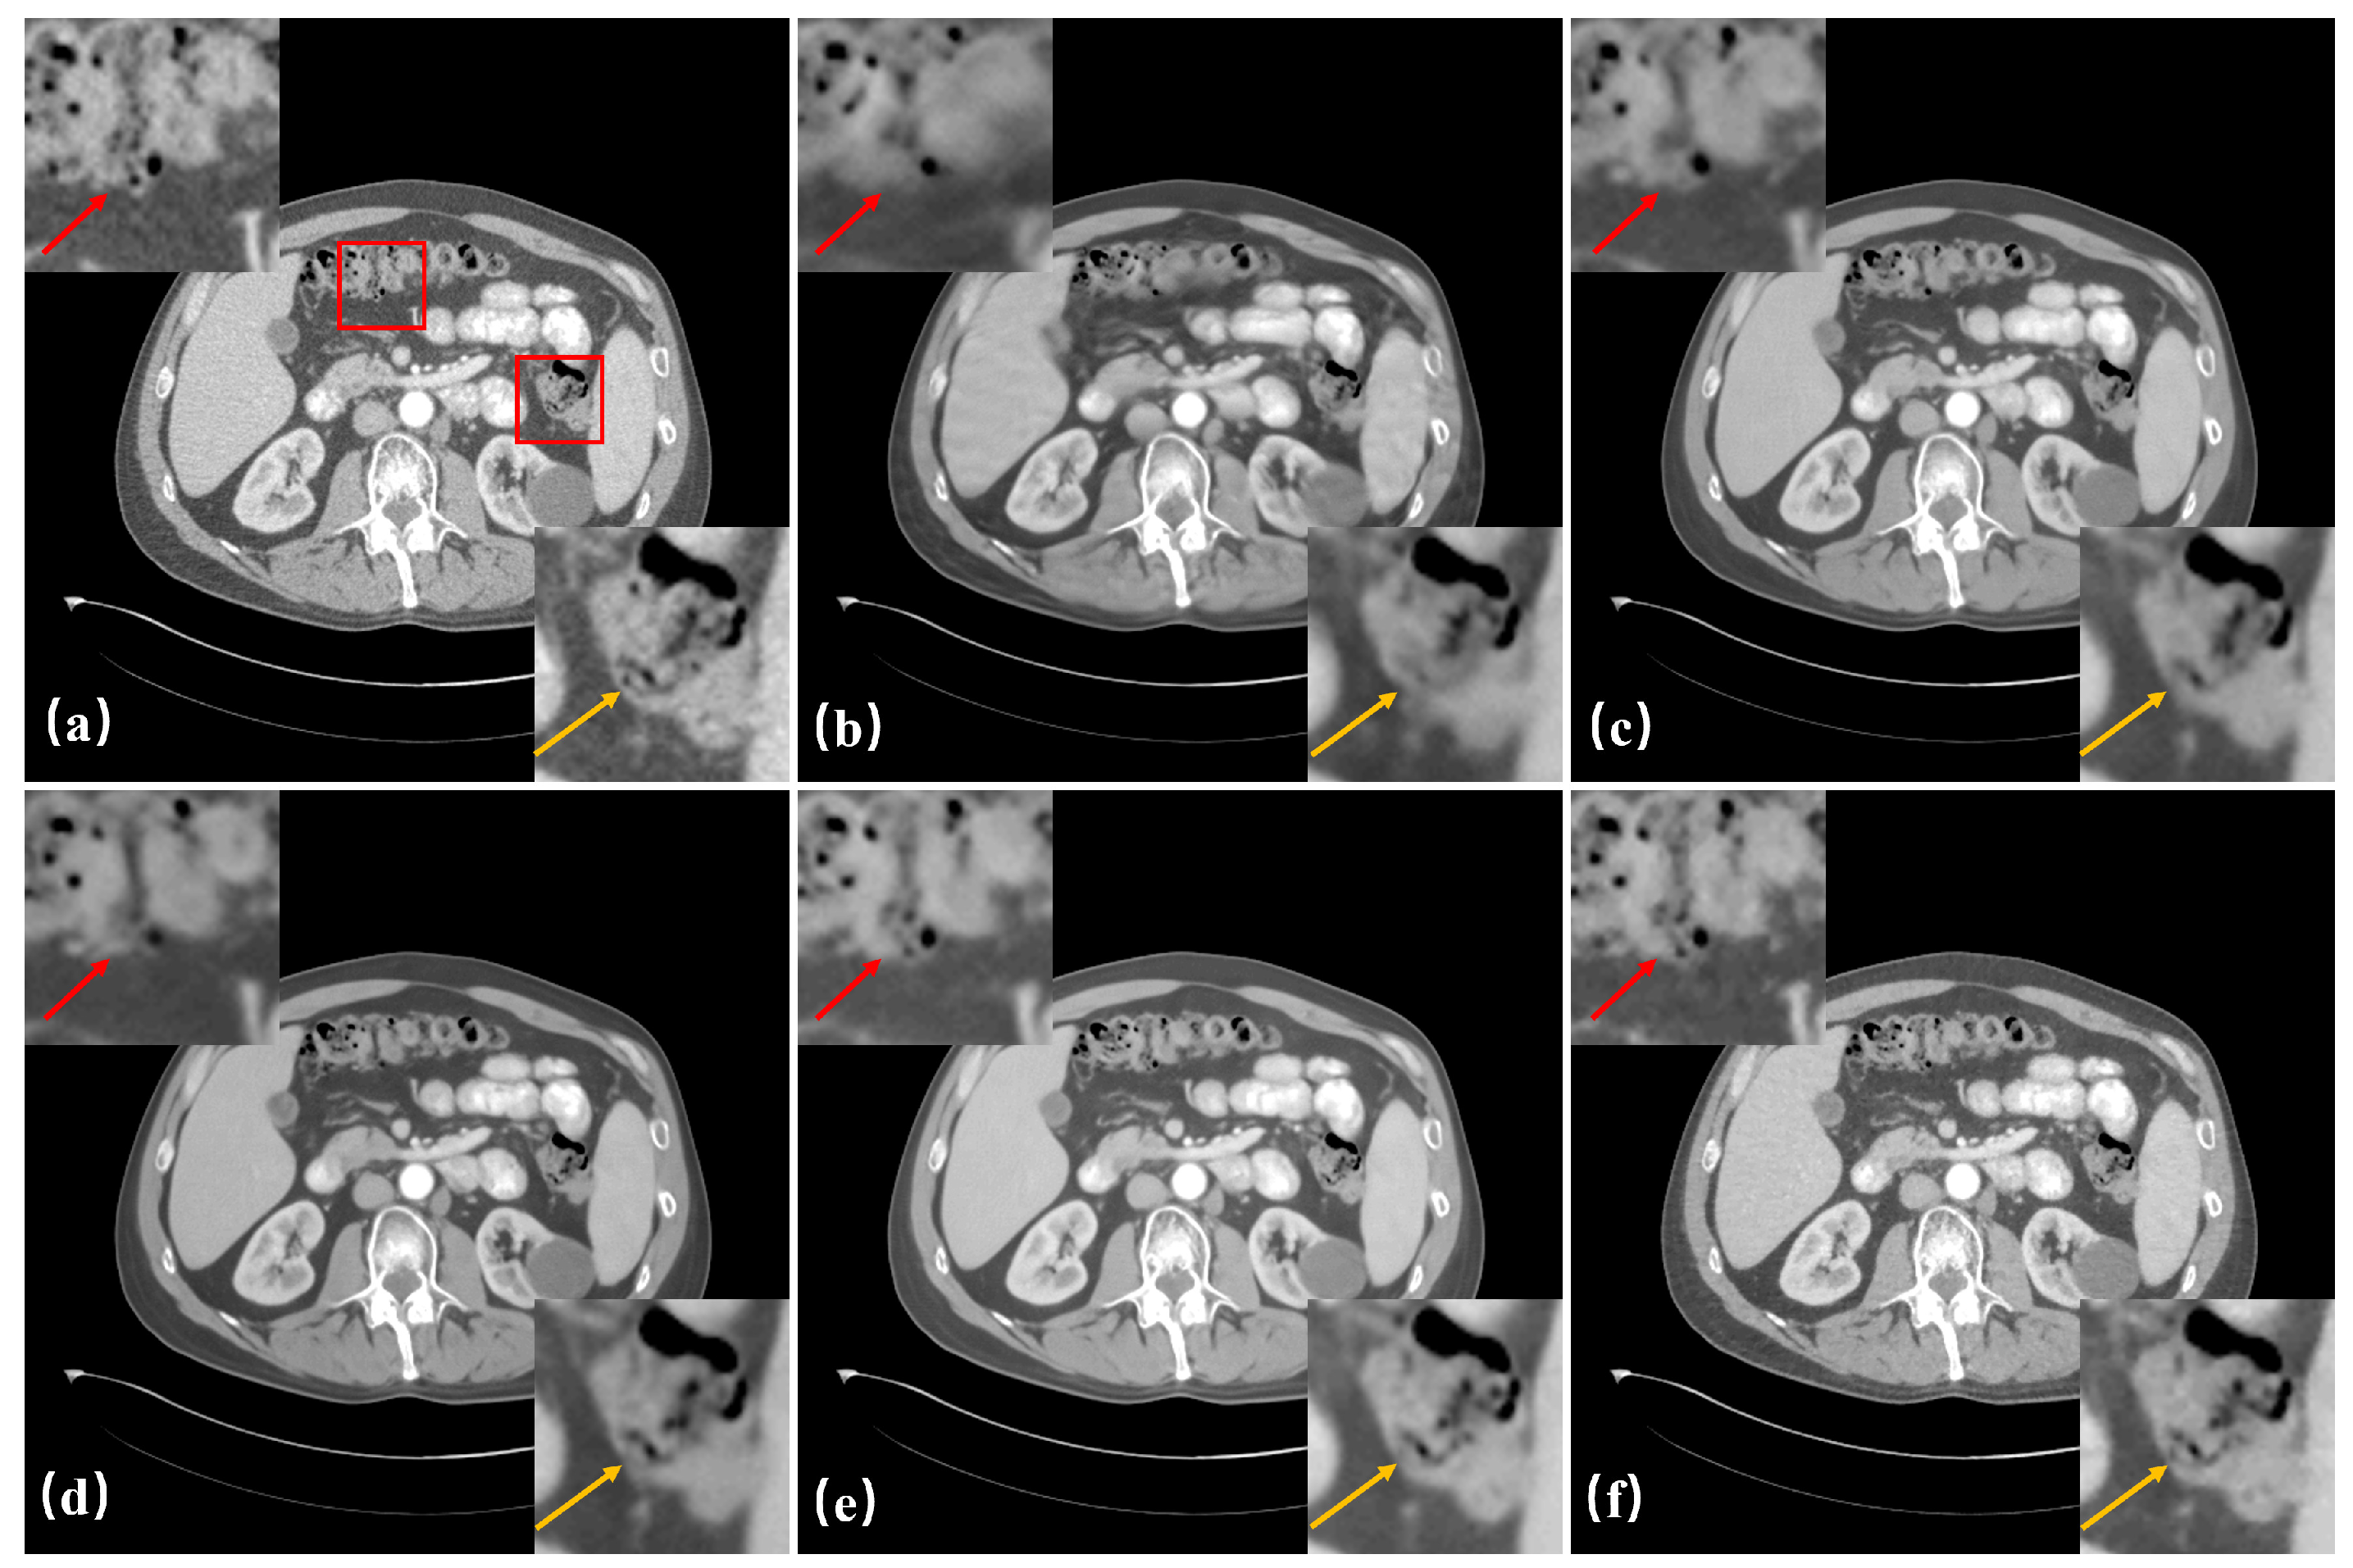

3.3. Results

3.4. Ablation Study